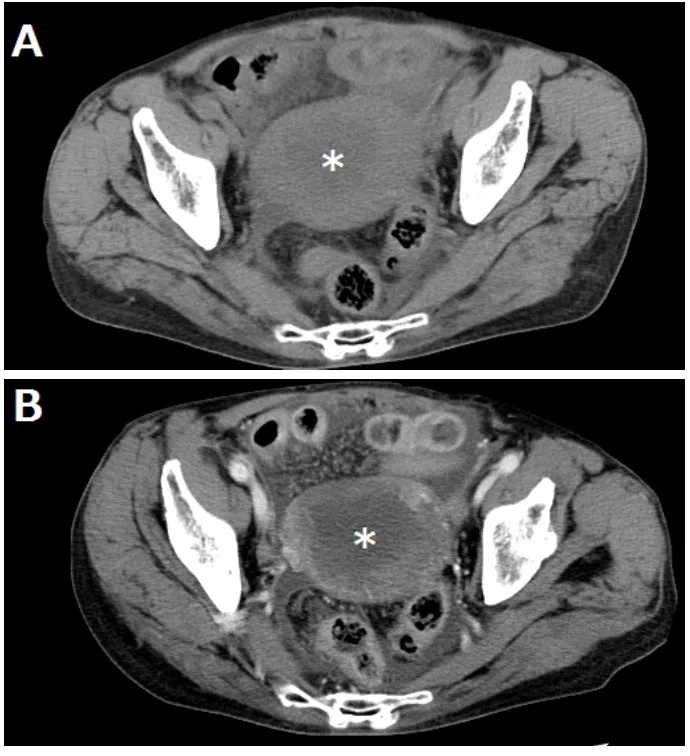

子宮留膿腫の患者

血液検査の結果, 貧血はありませんでしたが, 白血球が12,000/mm3, CRPが21 mg/dLと炎症反応が高値でした.

造影CTでは, 子宮の壁側が造影されて, 中央の膿は造影効果がありません.

引用元:勝又. 造影CT検査が診断に有用であった子宮留膿症穿孔の2症例. 静岡産科婦人科学会雑誌. 2015. 4.

熱源検索のために, 全身の造影CTを撮像したところ, 腸には異常なし, 子宮の中に造影される病変を認めました.

子宮留膿腫を疑って, 抗菌薬セフメタゾールを開始.

婦人科で診ていただくことにしましたが, 当院には, 婦人科がないため, 病診連携室で受診先をさがしてもらうことになりました .